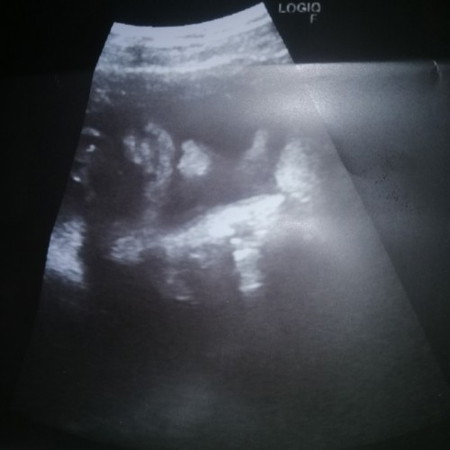

Asking lng po saan ang nose at lips ni baby hindi ko kasi alam. Hehe salamat po😊#pleasehelp

Yung bilog po bandang kanan is mukha niya.